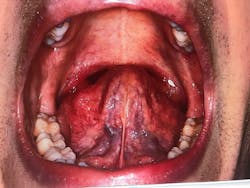

Figures 2 and 3: Crowding of the lower anterior teeth and scalloping of the tongue. These are common findings with airway and breathing disorders.

Figure 6: Extremely enlarged tonsillar tissue obstructing the posterior airway

Figure 7: Ankyloglossia—75% tongue-tie constriction

Figure 9: 95% obstructed posterior airway due to extremely enlarged tonsils